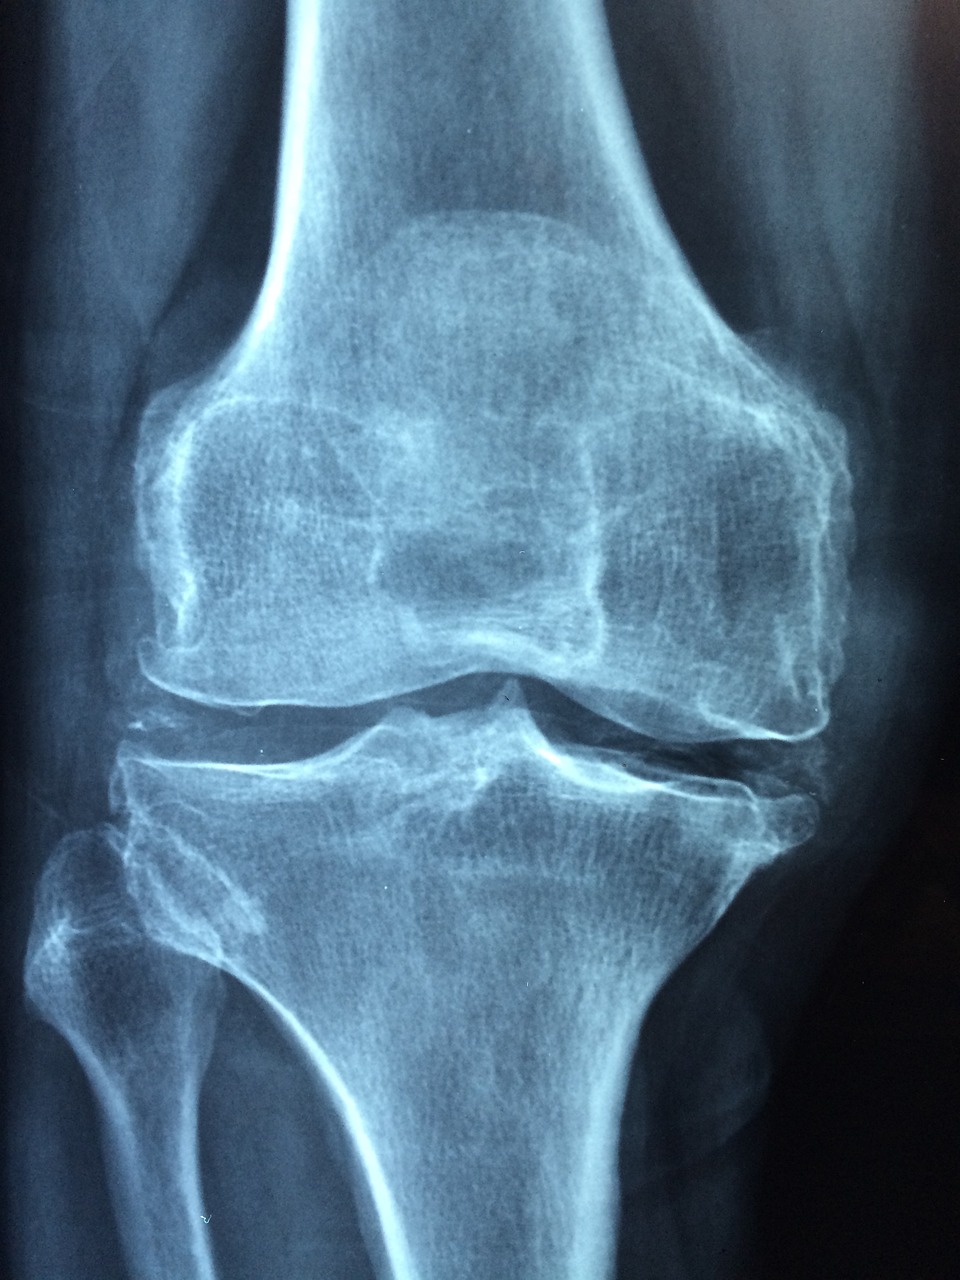

골다공증은 뼈를 구성하는 칼슘과 미네랄이 점차 줄어들면서 발생하는 만성 질환입니다. 외견상 뼈는 멀쩡해 보일 수 있지만, 내부는 점점 속이 비게 되며 아주 작은 충격에도 쉽게 골절이 발생할 수 있는 상태로 바뀝니다. 특히 여성은 폐경 후 에스트로겐 분비가 급격히 감소하면서 뼈 손실이 빠르게 진행되고, 이로 인해 골다공증의 위험성이 급증합니다. 남성도 나이가 들수록 뼈의 재형성 능력이 떨어지고, 흡연, 음주, 운동 부족 등 좋지 않은 생활습관으로 인해 골다공증 위험에 노출될 수 있습니다. 문제는 골다공증이 대부분 특별한 증상 없이 서서히 진행된다는 점입니다. 통증이나 불편함 없이 진행되다 보니, 골절이 발생한 이후에야 자신이 골다공증이라는 사실을 인식하게 되는 경우가 많습니다. 특히 척추나 고관절 부위의 골절은 회복 기간이 길고, 장기적인 활동 능력 저하로 이어져 삶의 질을 심각하게 떨어뜨릴 수 있습니다. 최근에는 30~40대의 비교적 젊은 연령대에서도 과도한 다이어트, 편식, 음주, 흡연 등으로 인해 골다공증 초기 증상을 경험하는 사례가 늘고 있습니다. 이와 같은 현실은 골다공증 예방과 관리가 더 이상 고령자만의 문제가 아니라는 점을 시사하며, 연령을 불문하고 평소 건강한 뼈를 위한 노력이 필요함을 보여줍니다.